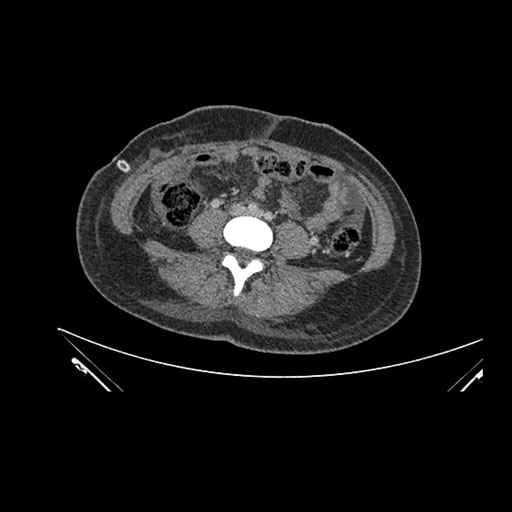

Axial Arterial

Axial Venous